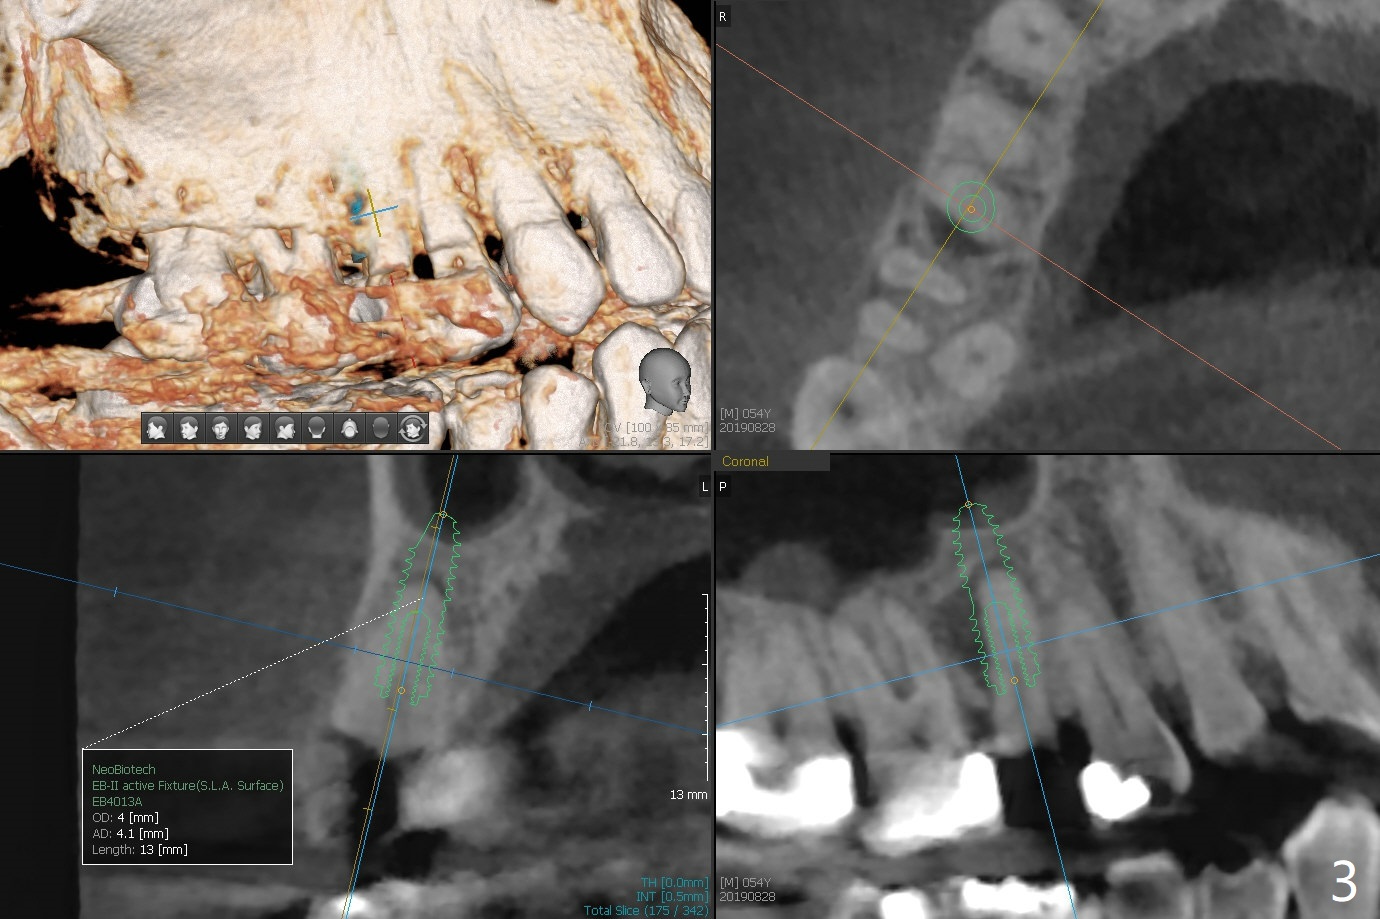

A 54-year-old man (smoker (3-4 cigarettes/day)) has two teeth that need to be replaced by implants (Fig.1). In order not to disturb the mucocele (Fig.1 *) above the tooth #15 to large degree, a short implant will be placed in the septum (not in the buccal socket (not disrupt the short buccal plate), Fig.2). Prepare PRFx1. Double check salvageability of the tooth #4. If needed, a 4.5x13 mm implant will be placed (Fig.3).